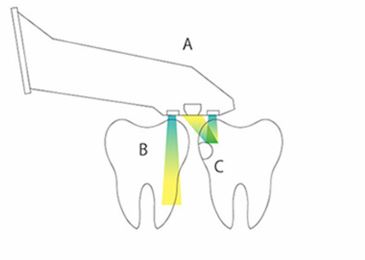

近赤外光画像(NIRI)技術で歯の内部構造をリアルタイムでスキャンしデータ化します。

普通のレントゲンでは心配という患者様に早期発見に役立ちますね。